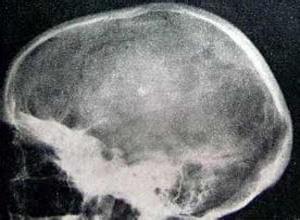

简介颅骨纤维异常增生症是一种有纤维组织替代骨质而引起颅骨增厚,变形的疾病。病变可只累及颅骨,也可同时累及身体其他部位的骨骼。